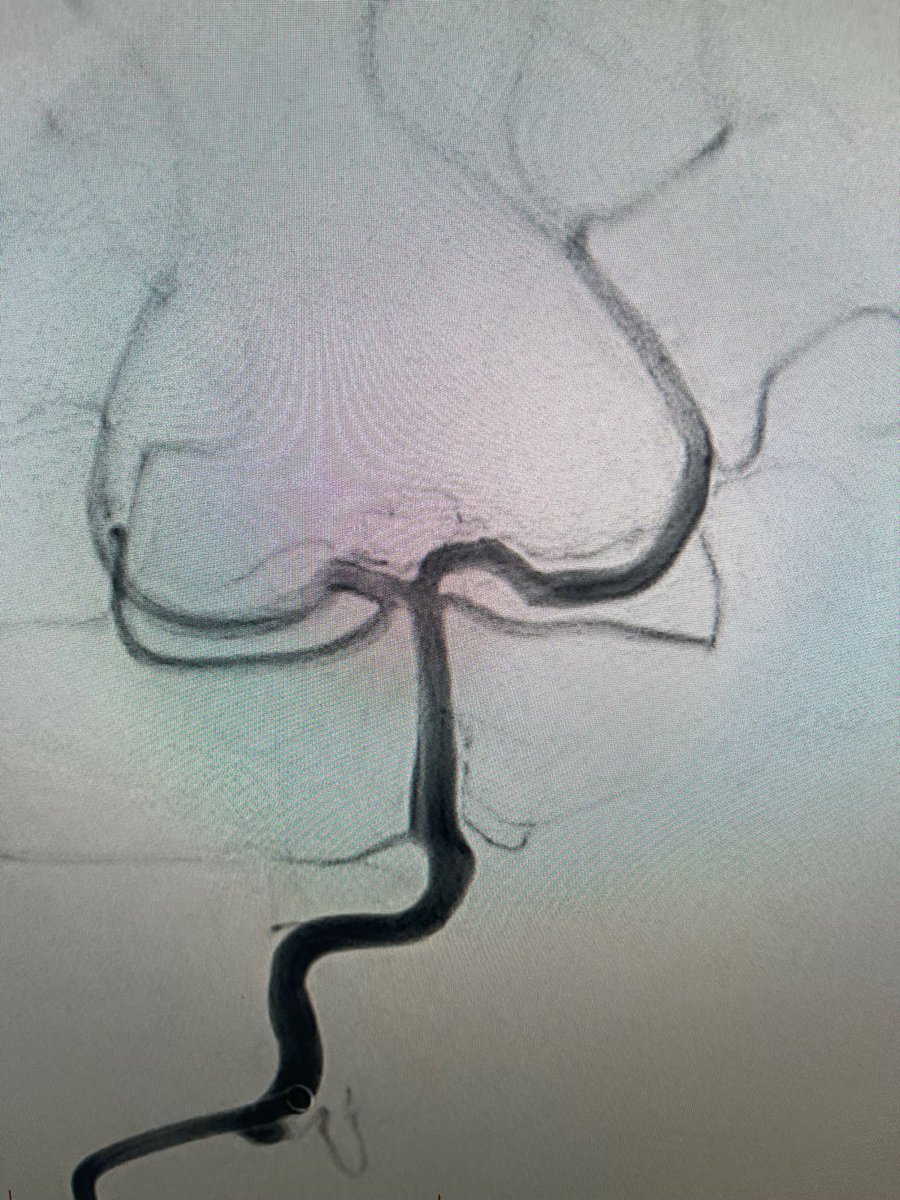

US HCPs: Check out this fantastic first pass result using RED 43 in left M2 from Dr. Amir Khan out of OC, CA! No clinical deficits or MRI infarct observed post thrombectomy. Thank you for sharing! #RED43 Rx only. Risk info: bit.ly/2BYj7Yj. Clinical results may vary.

PenNeuro's tweet image. US HCPs: Check out this fantastic first pass result using RED 43 in left M2 from Dr. Amir Khan out of OC, CA! No clinical deficits or MRI infarct observed post thrombectomy. Thank you for sharing! #RED43 Rx only. Risk info: bit.ly/2BYj7Yj. Clinical results may vary.